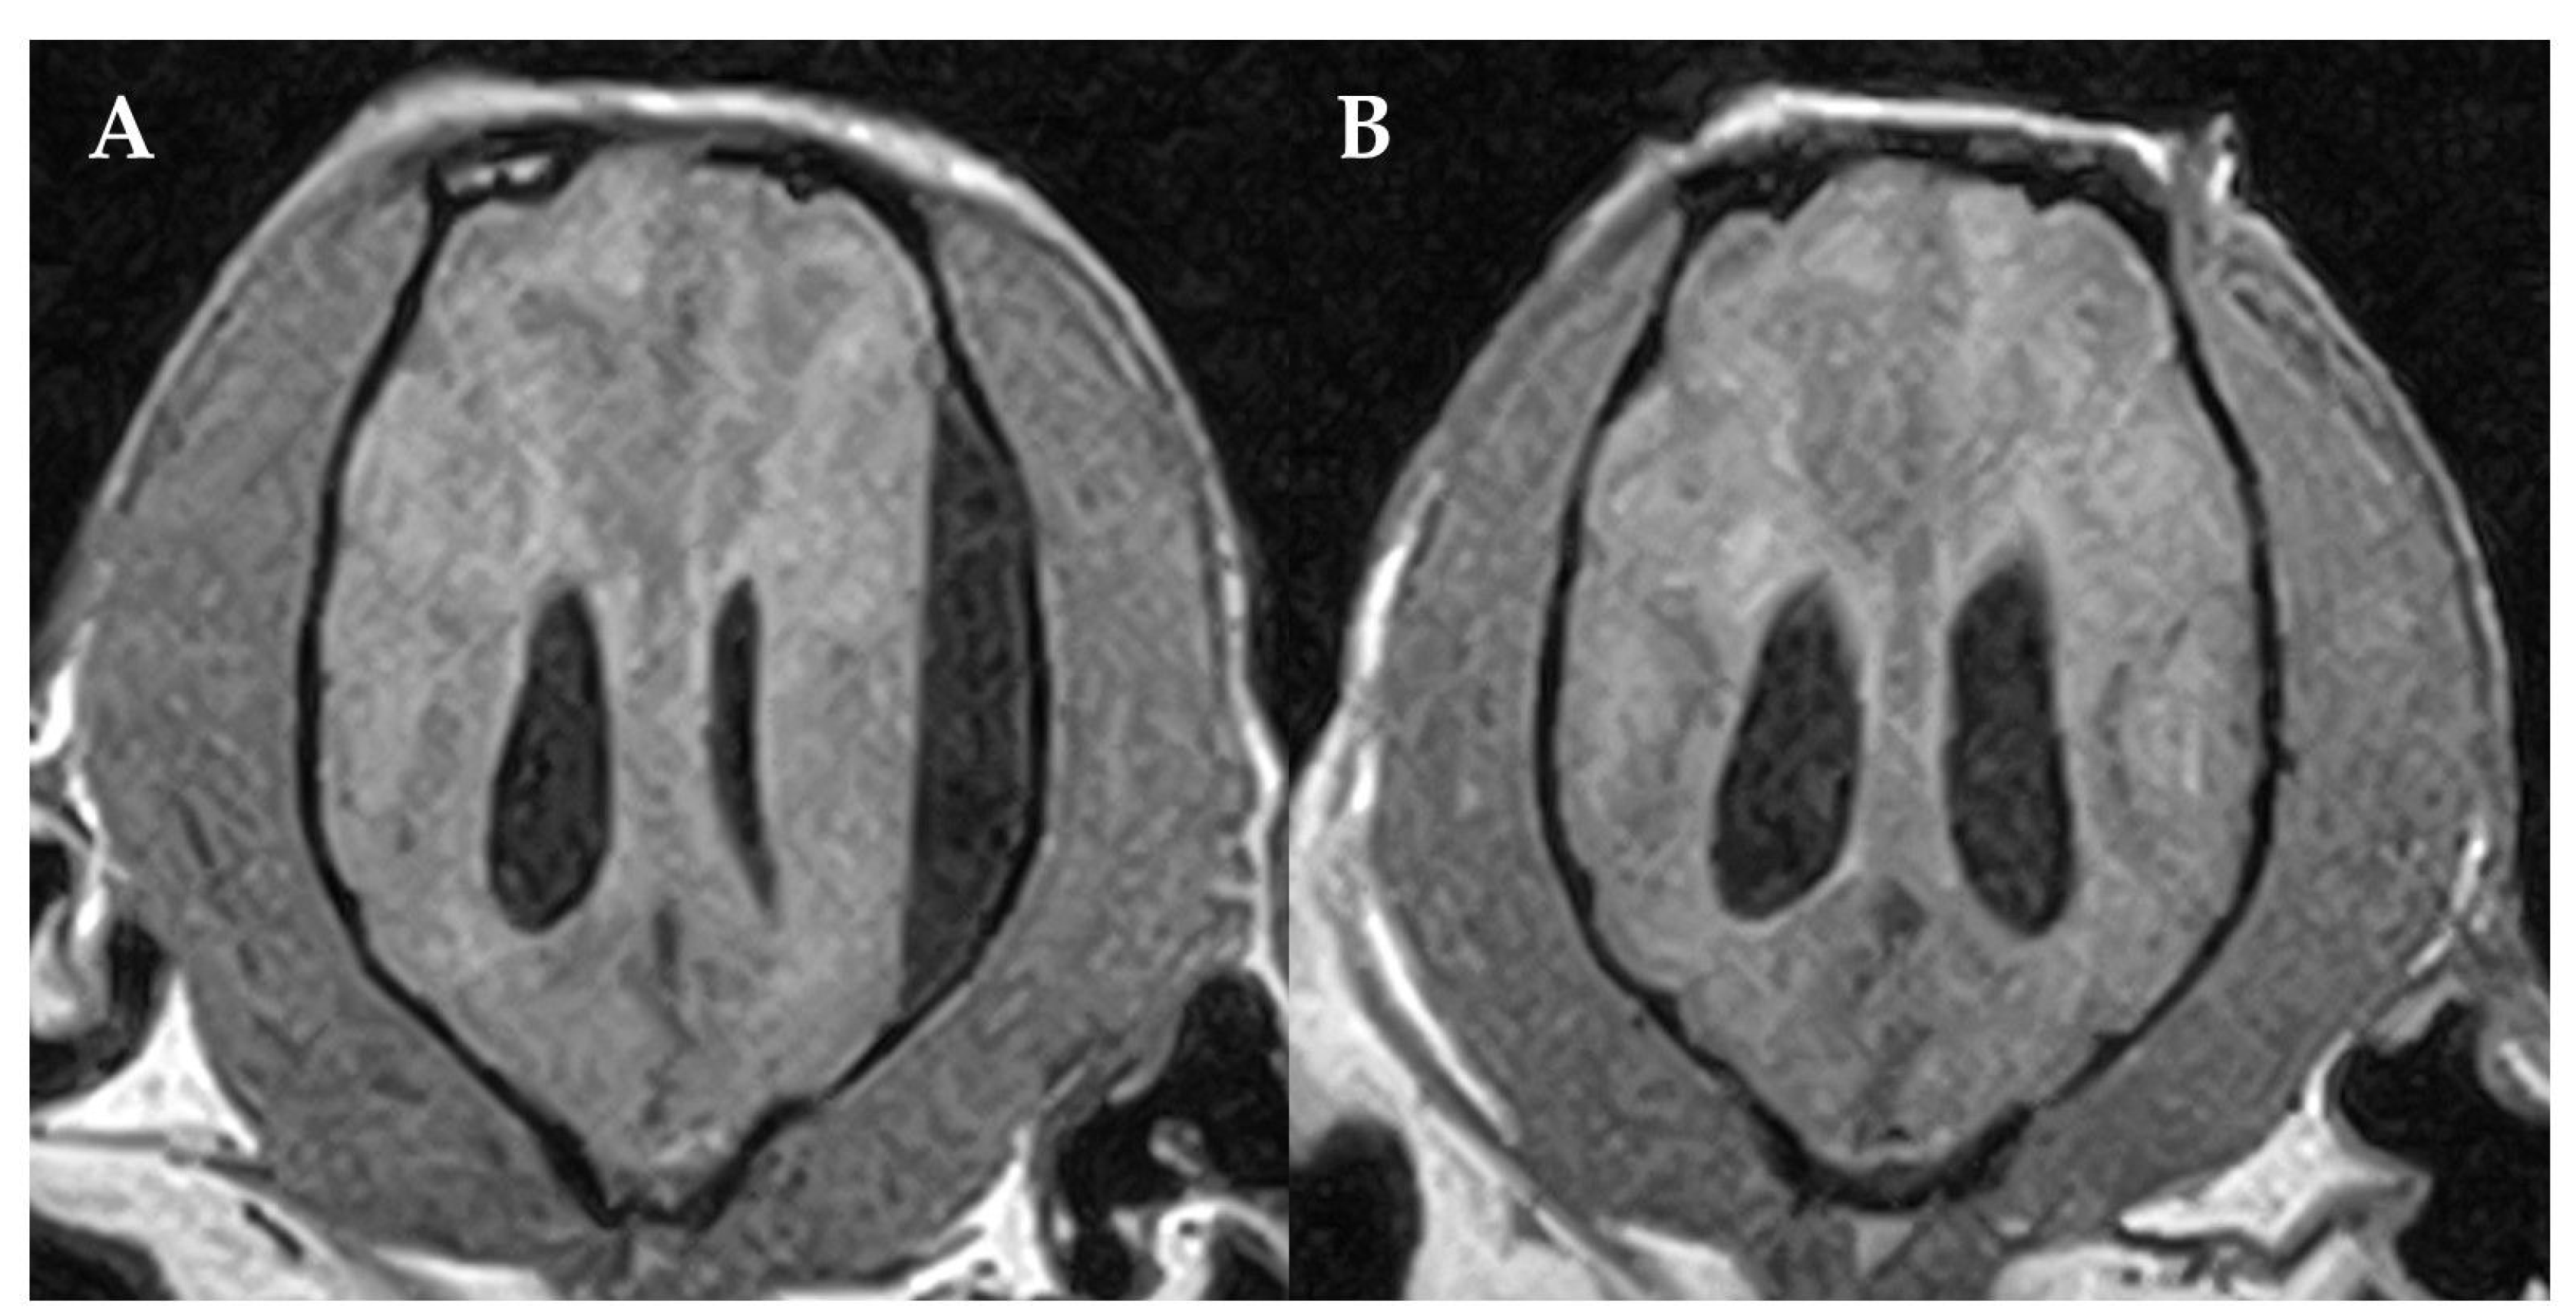

2. Case Presentation